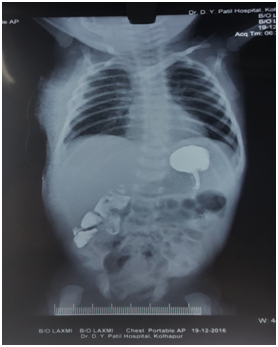

Postoperatively, patient was extubated after assessing the signs of full recovery. Paracetamol 40mg suppository was inserted per rectally and the patient was shifted to NICU for postoperative management. The baby was comfortable with stable vitals. Epidural analgesia with Inj. ropivacaine 0.2% 0.5 mg/kg, was repeated in boluses 6 hourly over 48 hours and then epidural catheter was removed (Figure 3). ABG on third postoperative day was normal. On tenth postoperative day barium swallow study was done and it was normal, no leak observed on X-ray chest and abdomen (Figure 4). The baby was discharged on 11th postoperative day when breast feeding was resumed. On telephonic follow-up he was well until 3months after surgery and also reported good weight gain of 500grams.

Figure 4 Postoperative X-ray Chest with normal chest findings after barium swallow study.